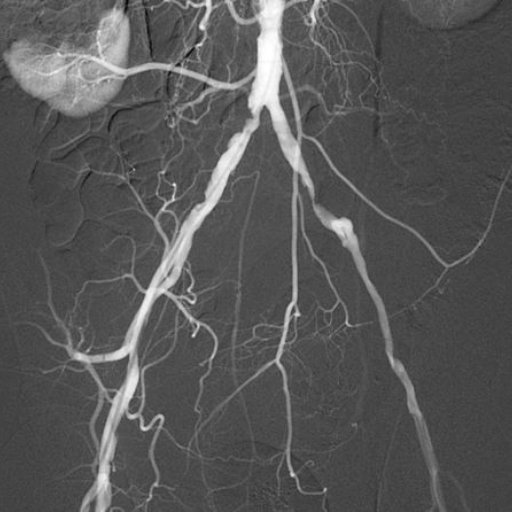

Es un estudio diagnóstico que permite visualizar las arterias mediante el uso de un medio de contraste y técnicas de imagen. Se utiliza para identificar estrechamientos, obstrucciones o alteraciones en los vasos sanguíneos, especialmente en las arterias coronarias, facilitando el diagnóstico preciso de enfermedades cardiovasculares y la planificación del tratamiento más adecuado.

Es un procedimiento diagnóstico y, en algunos casos terapéutico, que permite estudiar el funcionamiento del corazón y de las arterias coronarias mediante la introducción de un catéter delgado a través de un vaso sanguíneo. Este estudio ayuda a detectar obstrucciones, medir presiones dentro del corazón y evaluar el flujo sanguíneo, facilitando el diagnóstico y el tratamiento de diversas enfermedades cardiovasculares.